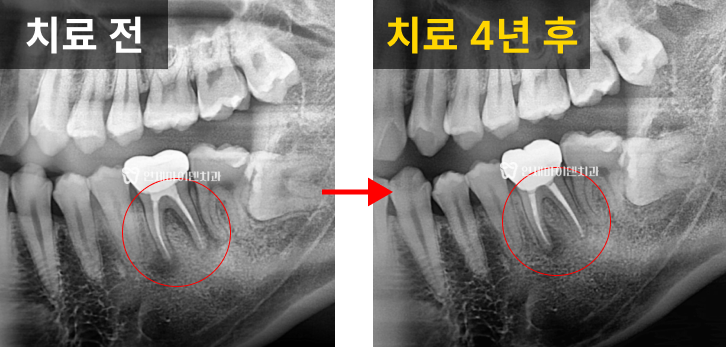

재신경치료 4년 후 경과

이 치아는 치료 2년 째 경과를 보면

치근 주변의 뼈가 완전히 회복된 모습을 모입니다.

그리고 무려 4년이 지난 후에도 염증의 재발 없이

자연 치아가 건강하게 유지되고 있습니다.

방사선상에서도 녹아 있던 뼈가 조금씩

하얗게 재생되는 것을 확인할 수 있었습니다.